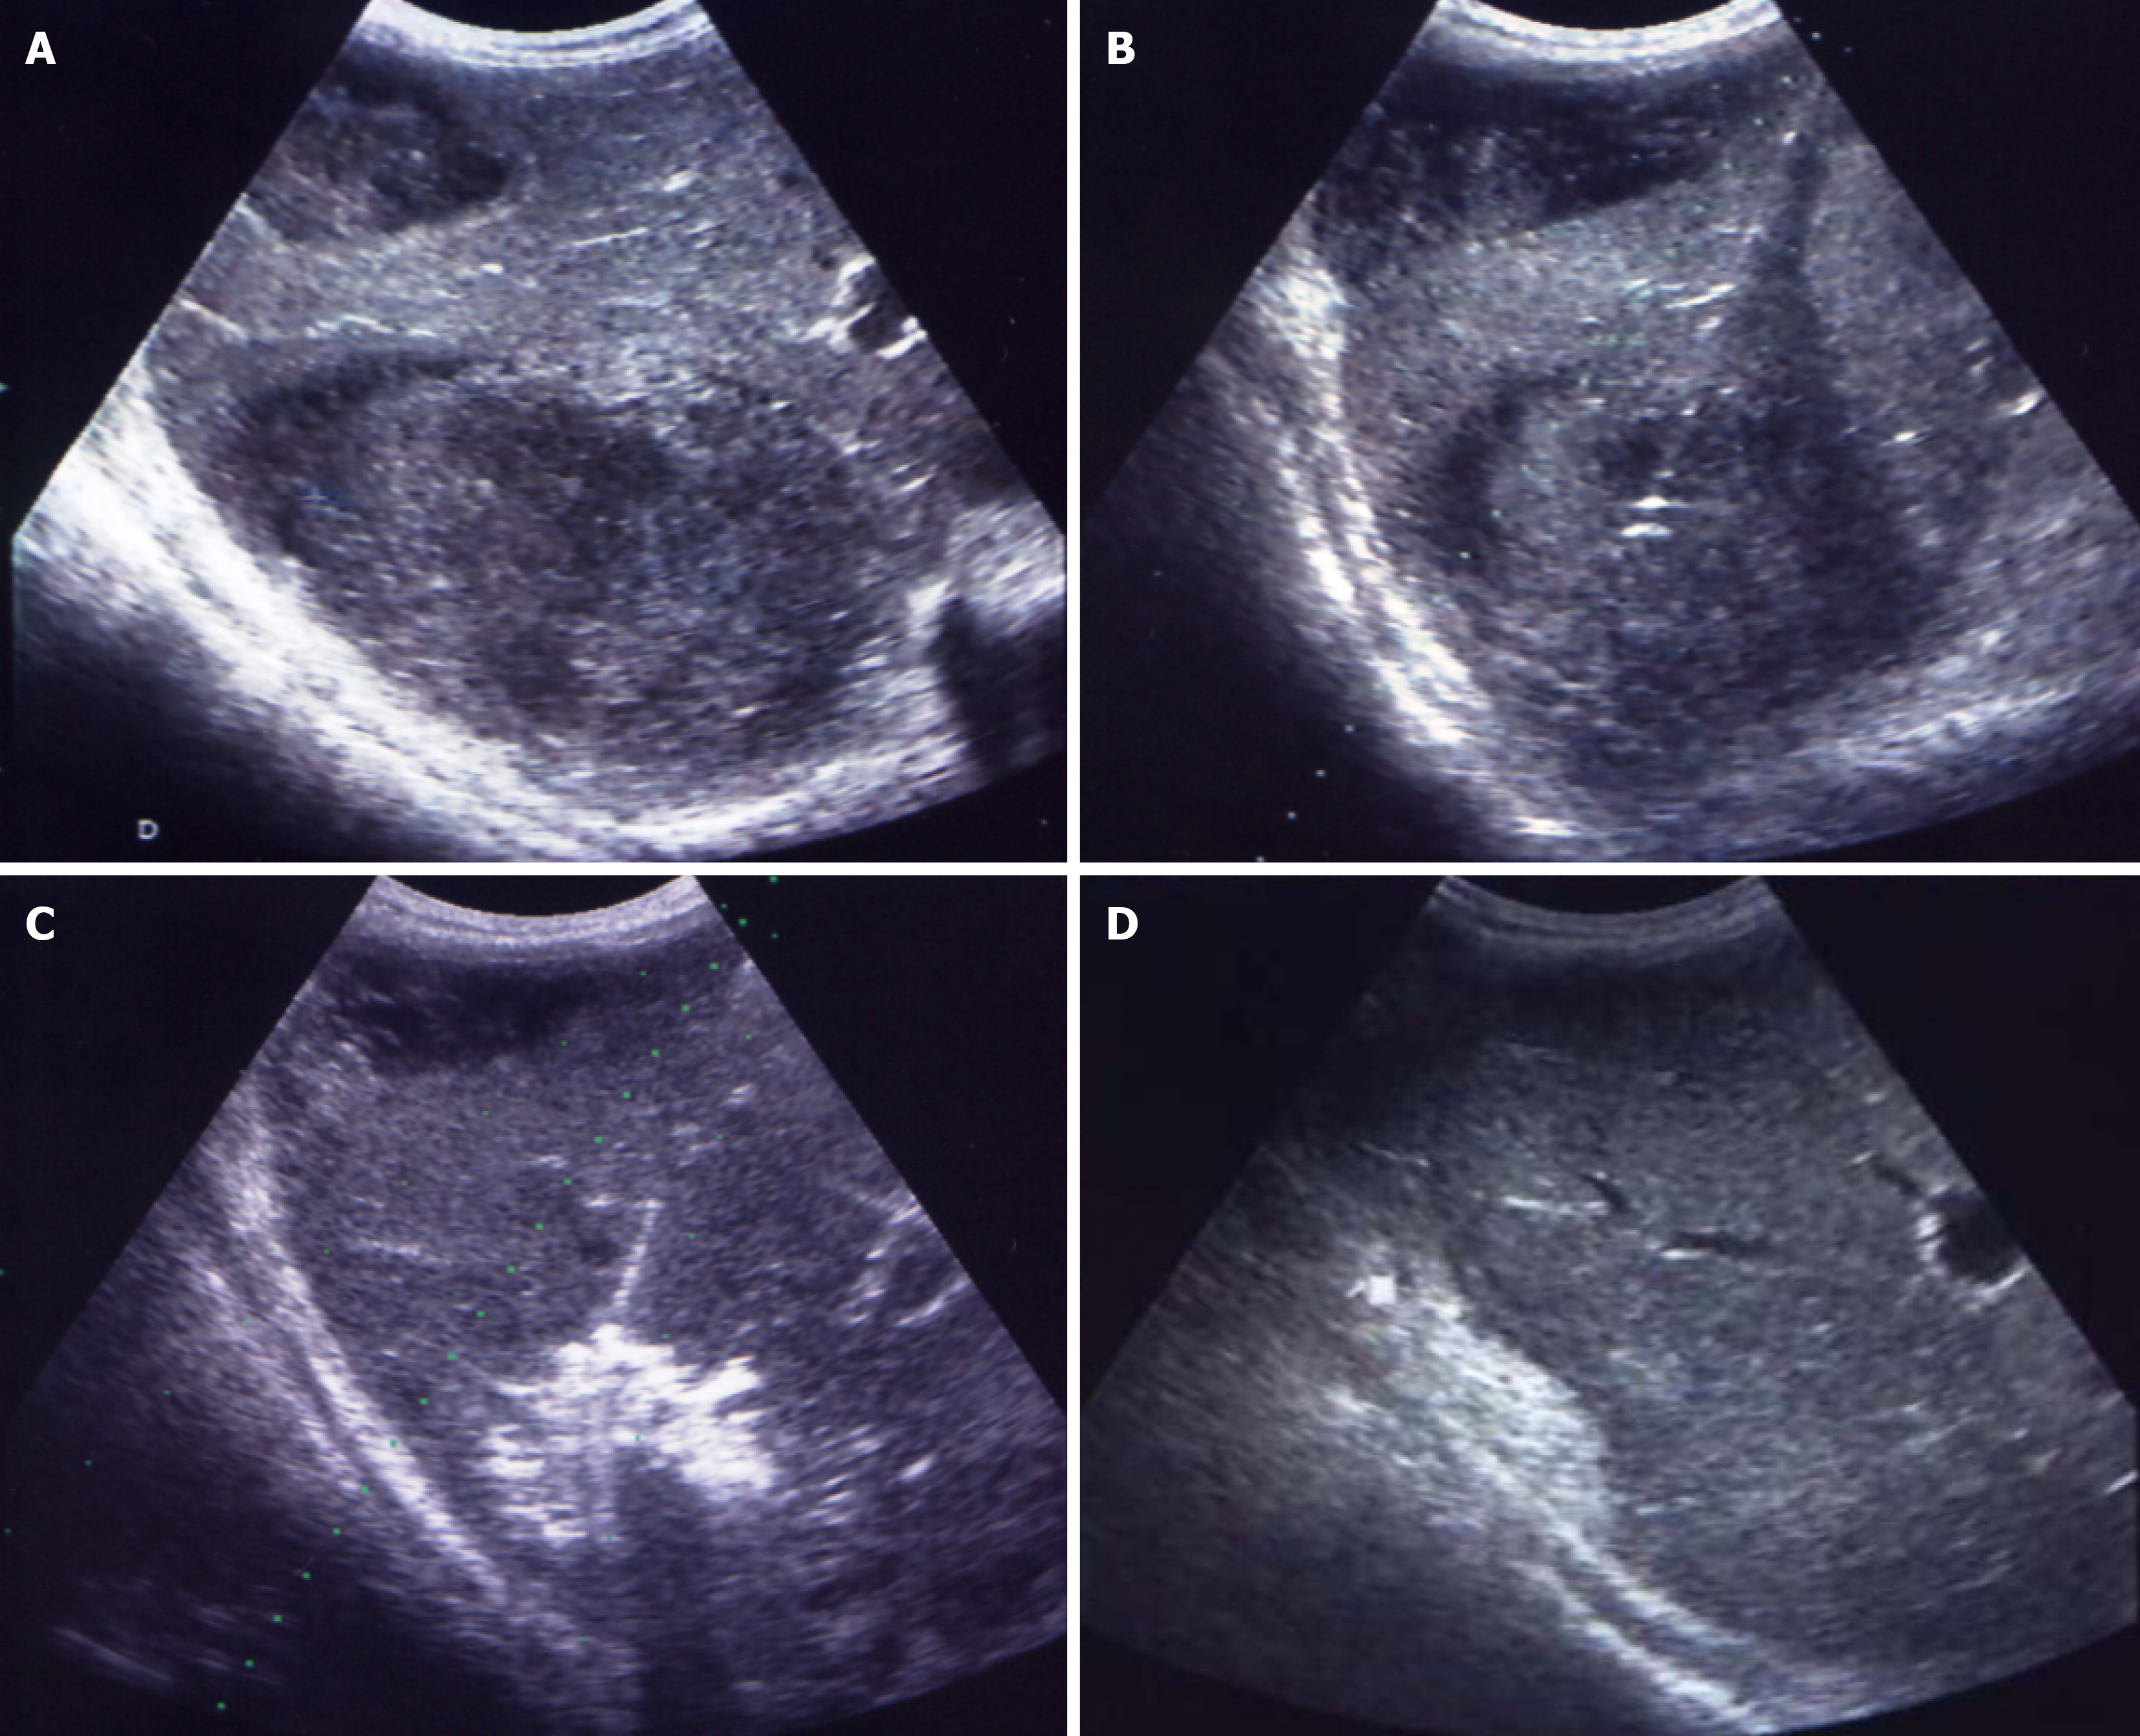

Microbiological etiology can also influence both the indication and success of early intervention. Anaerobes - often underdiagnosed due to culture limitations - are associated with polymicrobial infections and potential resistance to empiric therapy, which requires percutaneous intervention for diagnostic and therapeutic reasons. Early percutaneous intervention provides high-quality samples for culture, enabling timely adjustment of antibiotics[31,32]. Notably, some PLA, particularly multiple ones (Figure 1), may follow prior intra-abdominal interventions and be preceded by sepsis of unclear origin, making early intervention essential for pathogen identification and guiding targeted therapy[33,34]. Persistent bacteremia or poor response to therapy may indicate resistant strains, justifying intervention even in minimally liquefied collections[4-6,34,35].

Figure 1

Figure 1 Percutaneous treatment of multiple liver abscesses (a total of 10) using needle aspiration for those < 30 mm and catheter drainage for those > 30 mm. A and B: Abscess collections prior to the intervention; C: Catheter placed in one of the abscess collections; D and E: The same liver region six weeks after the intervention; F: Same patient as in panels A-E, with six catheters visible shortly after the procedure.